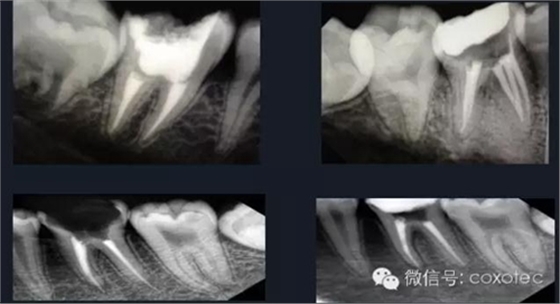

熱牙膠根管充填技術(shù)是利用牙膠加熱軟化后具有流動(dòng)性的特點(diǎn),使根管充填的效果更理想。

熱牙膠加壓充填技術(shù)是在加熱軟化牙膠尖的同時(shí),通過側(cè)向或(和)垂直向的壓力,將牙膠壓緊以嚴(yán)密封閉根管系統(tǒng)。以替代傳統(tǒng)冷的側(cè)方加壓充填的一種儀器。

由于它可以快速精確,密實(shí)的三維根管充填而受到醫(yī)生廣泛推崇,必將為根管充填帶來革命性的影響。

熱牙膠充填要點(diǎn)

①選擇符合根管錐度的主牙膠尖,標(biāo)記工作長(zhǎng)度后切斷牙膠尖端

0.5~1mm,并有確實(shí)的回拉感。

②去除距離根尖孔3~5MM以上牙膠。

③選擇合適的攜熱器,確定攜熱器工作長(zhǎng)度為根管工作長(zhǎng)度減去3-5毫米。

④選擇合適的垂直加壓器,并確定加壓器工作長(zhǎng)度,多把加壓器長(zhǎng)度遞減配合使用。

⑤選擇合適的熱牙膠充填器頭,標(biāo)記好需要充填的長(zhǎng)度。

⑥將根管內(nèi)注入樹脂類根管封閉劑后,再將牙膠尖放入根內(nèi)。

⑦使用手用加壓器垂直擠壓致密,垂直加壓器應(yīng)該從大號(hào)至小號(hào)。

⑧注射手法:輕,穩(wěn),慢